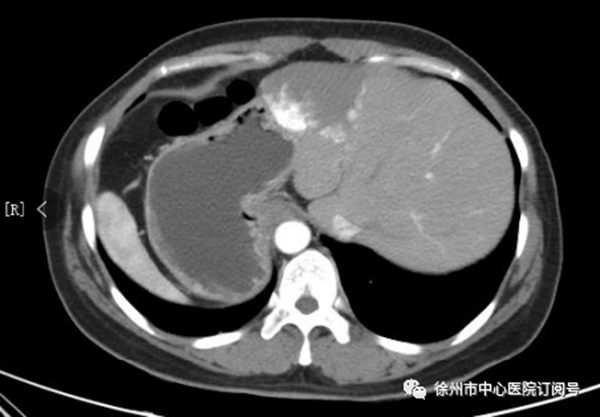

患者的肝臟位置和正常人完全相反